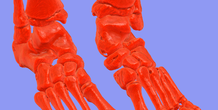

foot bone

by imlab

Bone of human foot that was created from DICOM images. This model has been generated support. Ready to print by 3D printer.